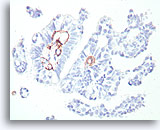

Papilloom, Borst FNA, Celblok.

Immunokleuring met p63 van de coupes van de patiënt in afbeelding 23-25 helpt de myoepitheliale cellen te markeren die door deze papilloom verstrooid zijn.

10X

Papilloom, Borst FNA, Celblok.

Immunokleuring met p63 van de coupes van de patiënt in afbeelding 23-25 helpt de myoepitheliale cellen te markeren die door deze papilloom verstrooid zijn.

10X

Papilloom, Borst FNA, Celblok.

De myoepitheliale cellen vormen nagenoeg continue rijen onder de ductale cellen (immunokleuring met p63).

40X

Papilloom, Borst FNA, Celblok.

De myoepitheliale cellen vormen nagenoeg continue rijen onder de ductale cellen (immunokleuring met p63).

40X